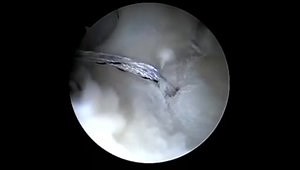

Labral Repair Made Simple

2018年9月25日

vumedi.com

Labral Repair

已浏览 1.1万 次